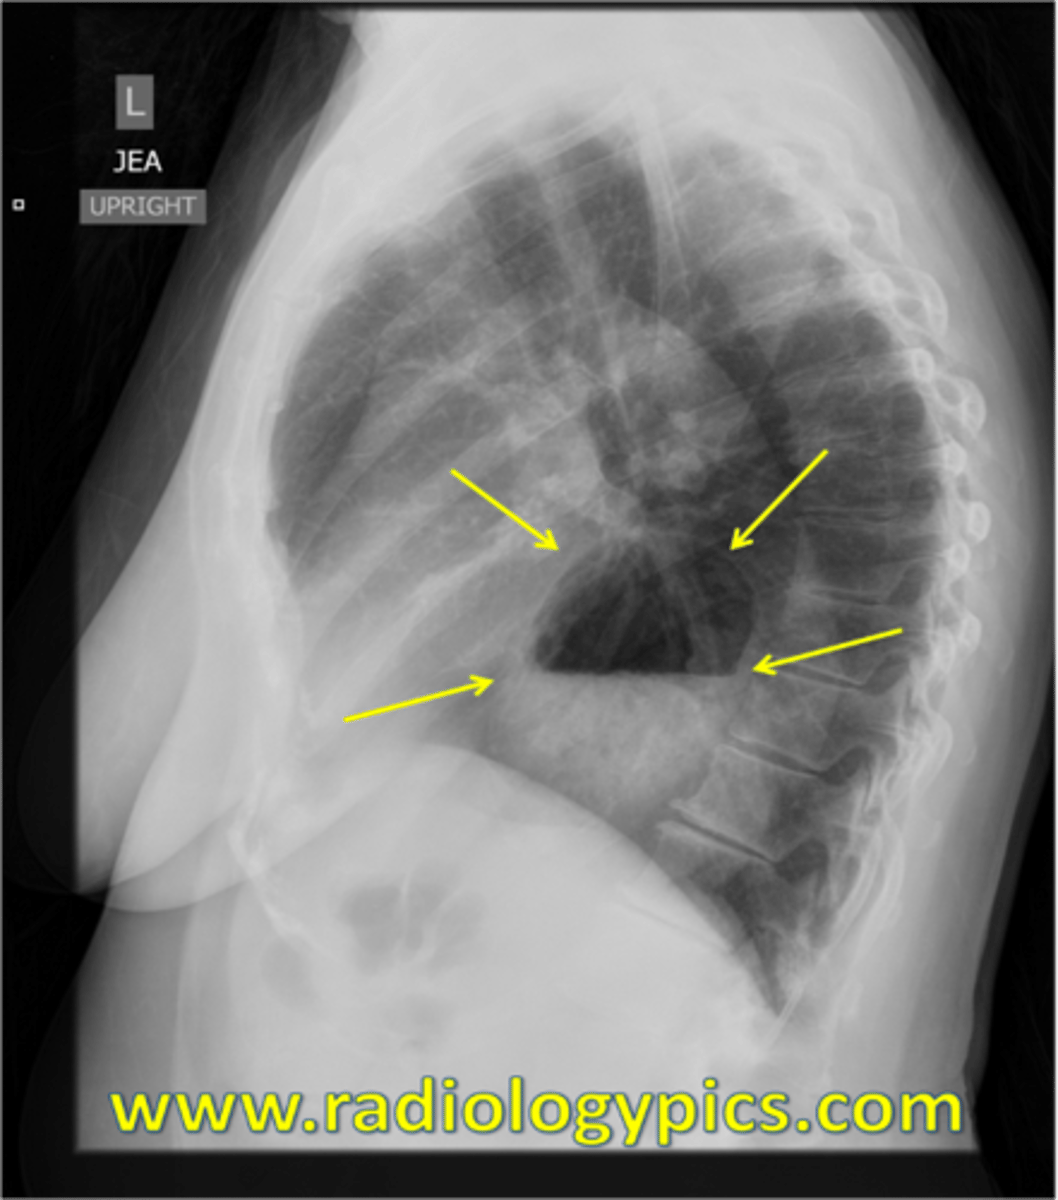

Sliding hiatal hernia

Sliding hiatal hernia (pic 2)

Sliding hiatal hernia (pic 3)